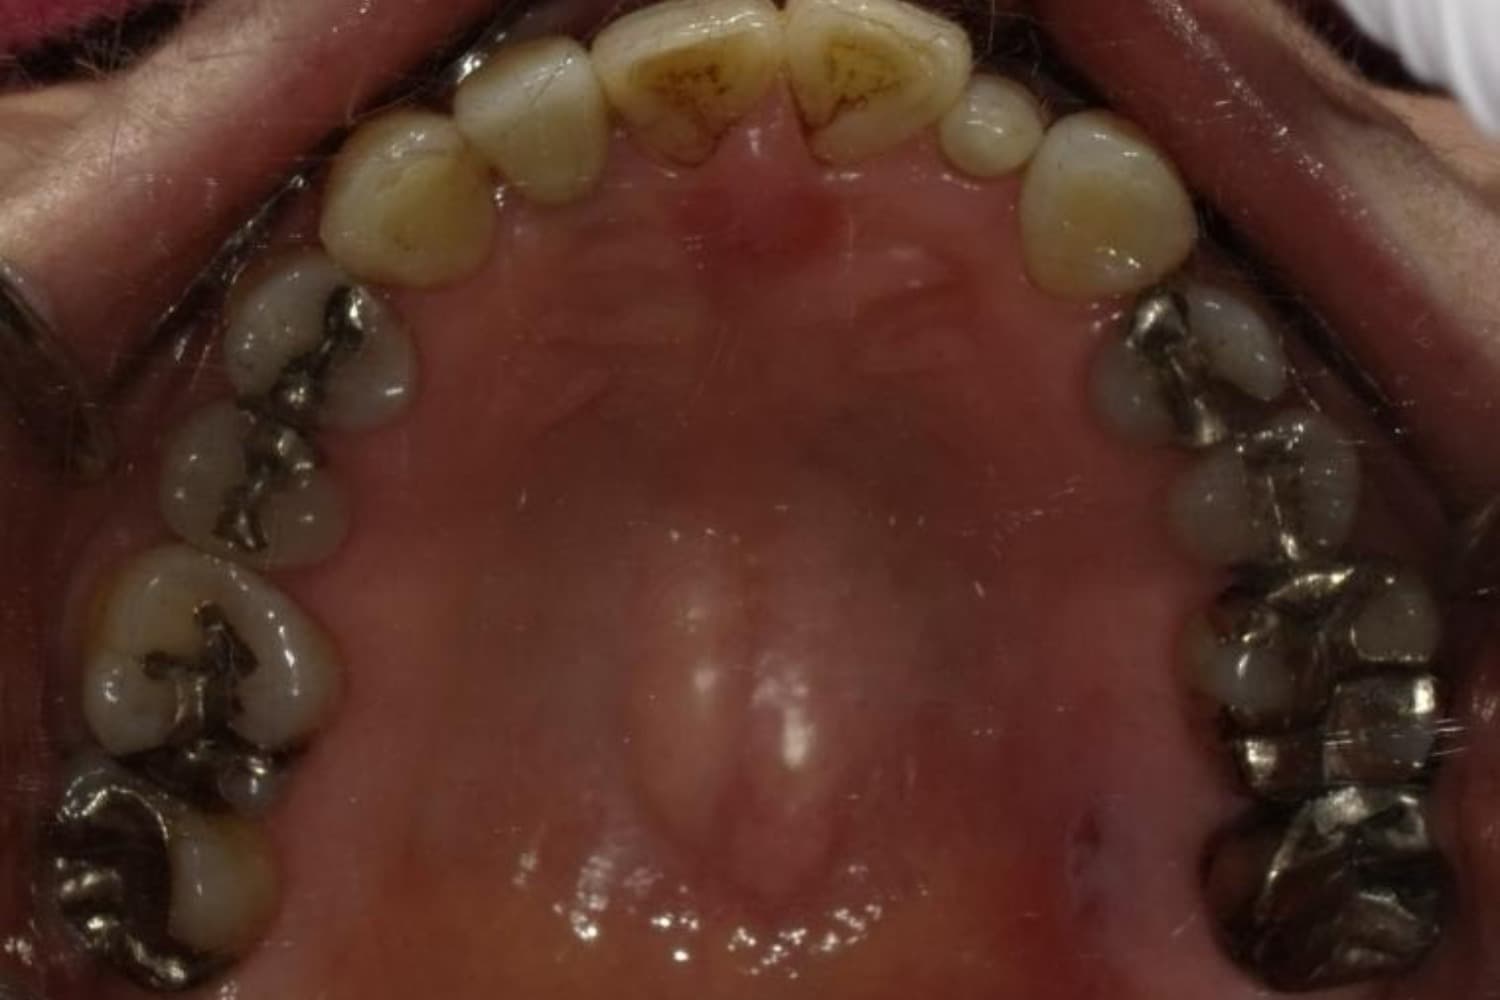

下顎大臼歯3本欠損症例

Before

After

左下第一大臼歯は保存が困難な状態であったため抜歯をおこないました。あわせて、ご来院時から欠損していた右下第一・第二大臼歯も含め、欠損部の補綴方法についてご説明し、インプラント治療を選択されました。

年齢

60歳

性別

男性

主訴

左下の第一大臼歯は別の医院で治療中でしたが、治療が思うように進まず、加えて他の箇所にも痛みが続いたことから、当院にご相談いただきました。

治療期間

10ヵ月

費用

140万円

副作用・リスク

インプラント治療は外科的な処置を伴い、多少の腫れや痛みが出ることがあります。 多くの場合は鎮痛薬で和らげることができます。